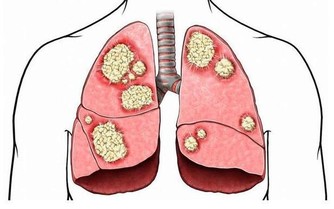

腎臟好比是身體的“淨水機”,每天過濾和清潔200升血液,

把有用的東西留在血液中,讓代謝的廢物排出體外。

別看腎臟功能強大,卻是一個脆弱的器官。

調查顯示,我國慢性腎病的發病率逐年上升,城市中每10人就有一例,

因此,我們應該時刻關注腎臟健康,留意它發出的“維修”信號。